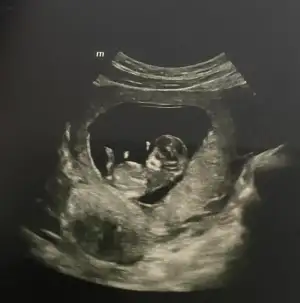

Benim nedir sizce 11+1Erkek bence

Bu bebis de erkek gibi geldi bana ama bilemedim yine de :))Benim nedir sizce 11+1

Ay benimde 12 +1 bana da tahminde bulunabilir misinizKız gördüm sanki, sağlıcakla gelsin

Yüz üstü durmuş sankiAy benimde 12 +1 bana da tahminde bulunabilir misiniz![]()

Evet yüz üstü yatıyor o yüzden doktorda bişey diyemedi belki sizin bi tahmininiz vardır diye sormak istedimYüz üstü durmuş sanki![]()

Benim attığımı da tahmin eder mısınız 11+5Bariz erkek görüyorum, sağlıcakla gelsin inşallah![]()

Erkek görüyorum sağlıcakla gelsin inşallahBenim attığımı da tahmin eder mısınız 11+5